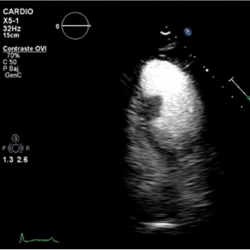

Figure 2.

Echo-contrast was administered, showing perfusion of the mass, excluding the diagnosis of thrombus.

Conventional transthoracic echocardiography was repeated a week later, without changes. 2D-echocardiographic study was completed with intravenous echocardiographic contrast to demonstrate perfusion of the mass, excluding the diagnosis of thrombus (Movie II in the Data supplement) and with 3D echocardiography for better visualization and establishing spatial relationships of the mass (Movie III and Movie IV in the data supplement).